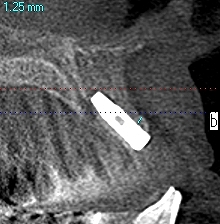

右上3番のインプラント埋入CT

13㎜のインプラントを埋入しています